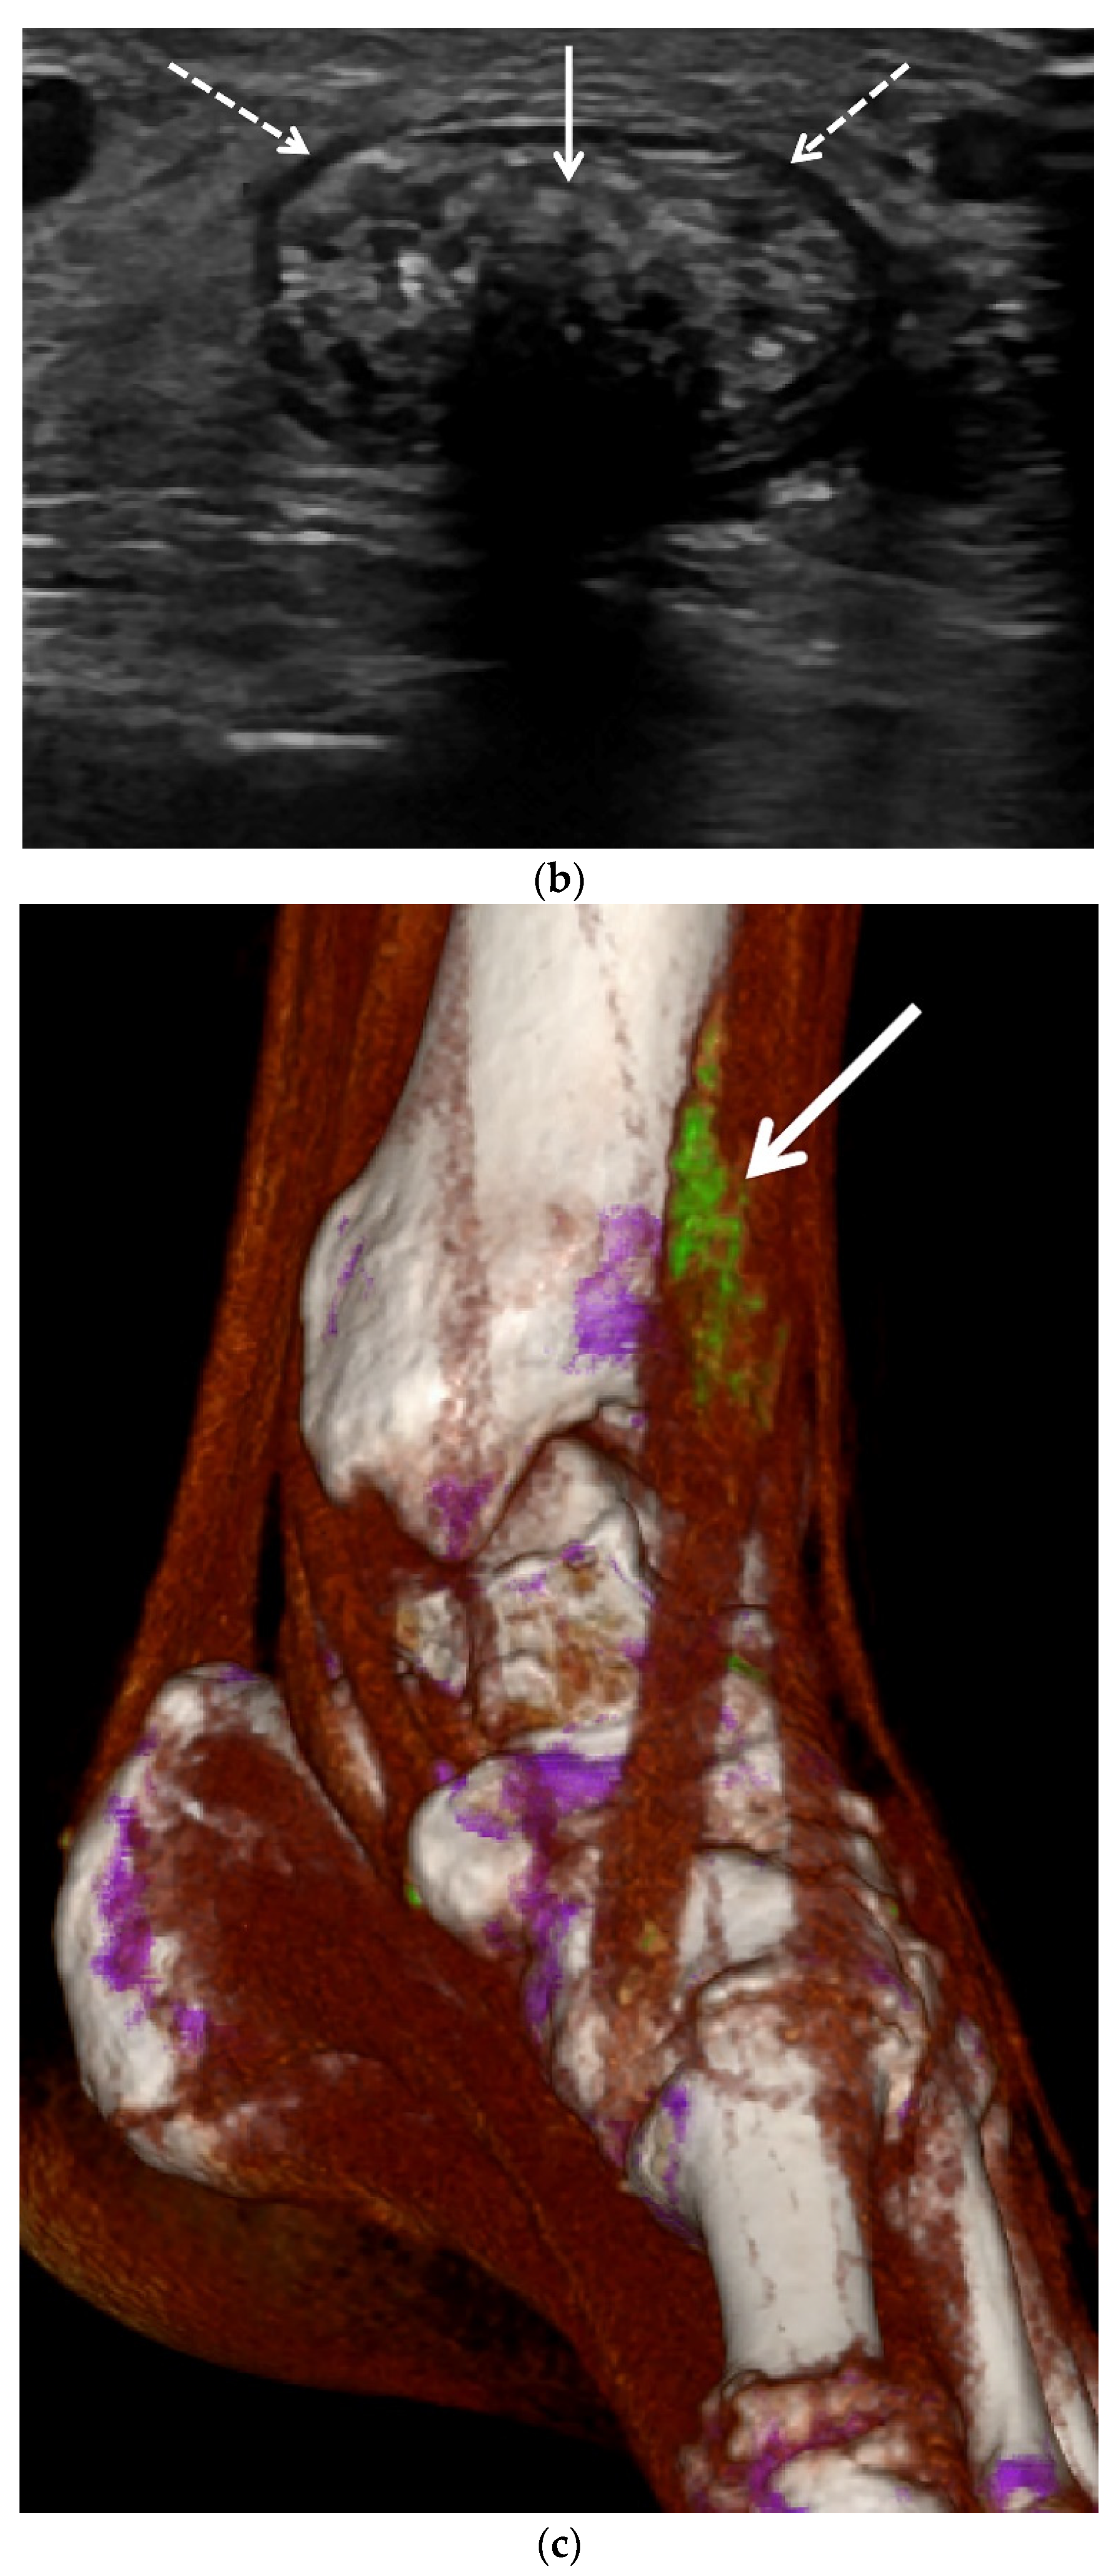

3.2. Ultrasound (US)

3.3. Computed Tomography (CT): Conventional and Dual Energy (DECT)